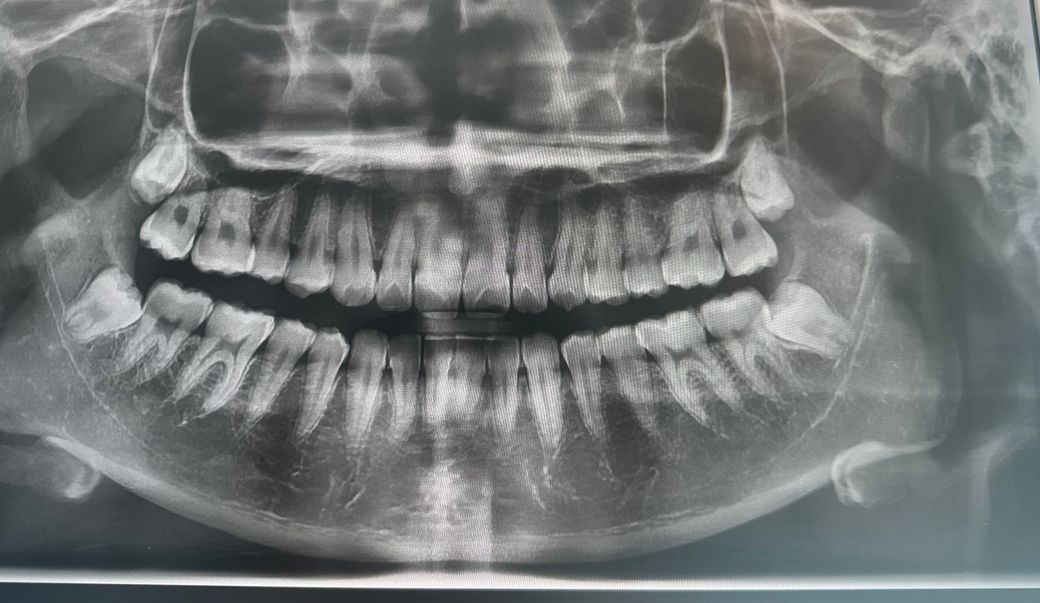

제 사랑니 엑스레이 어때보이나요??

최근에 치과에 가서 엑스레이를 찍었는데 사랑니가 신경에 닿아있는것 같아서요ㅠㅠ 대학병원 가서 뽑아야할 정도일지 좀 봐주세요!!

정확한건 CT를 찍어봐야 알겟지만 엑스레이 상으로는신경과 거리가 가까워 보이긴합니다.

아래 사랑니 2개는 완전매복에 신경관이랑 거의 겹쳐있네요 대학병원가서 뽑는다고 뾰족한 수가 있는 것은 아닙니다. 일반 치과에서도 ct찍고 최대한 신경 손상 주의하면서 빼면 되고 이건 대학병원에서도 마찬가지입니다.